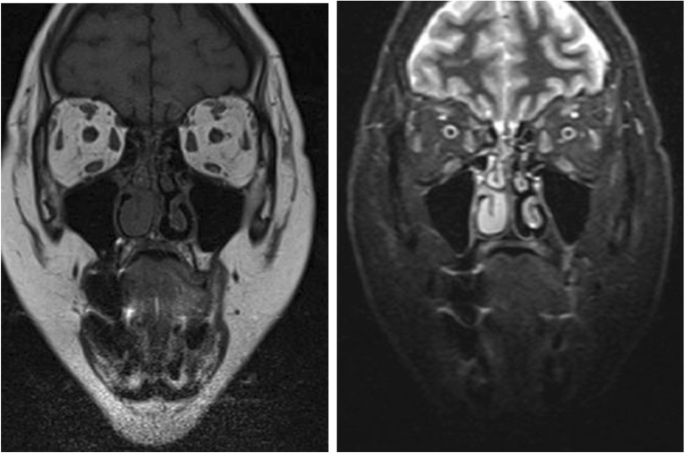

Patient was regularly followed every 2 weeks to ensure compliance, assess evolution and determine potential side effects. Upon the completion of 2 months treatment with oral prednisone a marked regression of the palpebral edema was noted with no further deterioration in her visual acuity. An orbital MRI was performed upon completion of oral therapy and showed a resolution of the edematous anomaly of the right lower muscle, absence of extraocular muscles signal abnormality with symmetrical globes and regression of the grade II proptosis to the right (Fig. 3). In addition, biological markers evaluation was performed upon the completion of oral therapy and showed minor metabolic side effects of the treatment namely a mild elevation in total cholesterol and LDL levels (Table 2). Furthermore, thyroid function evaluation upon completion of treatment was notable for a slight increase in TSH with normal FT3 and FT4 (Table 2). Even though, steroids are usually associated with a decrease in TSH level through its effect on TRH [3]. However, in our case TSH level slightly increased after completion of steroids treatment with normal FT4 falling in subclinical hypothyroid range; hence, suggesting the diagnosis Hashimoto’s Thyroiditis. Patient was scheduled to have a follow-up visit every 3 months for the next 1 year in order to monitor for development of overt hypothyroidism requiring further treatment. No weight changes were recorded. At 6 months follow-up patient was symptom free with no ocular proptosis, no further deterioration in her visual acuity beyond the baseline and a minor residual right palpebral edema (Fig. 4) with a clinical activity score of 1. The patient equally reported an improvement in her asthenia and a reduction in frequency of her tension headaches.